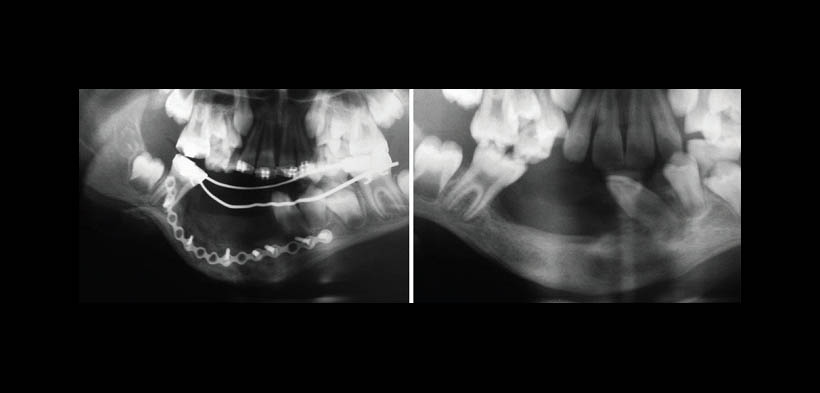

Fig. 3. Radiografía panorámica en el postoperatorio inmediato, y al año del tratamiento quirúrgico, se puede observar poco hueso alveolar en las dimensionas verticales.

Fig. 4. Distracción osteogénica del hueso alveolar para ganar altura del reborde alveolar y la planificación futura de implantes dentales. Procedimiento realizado a los 4 años del diagnóstico inicial de GCCG.